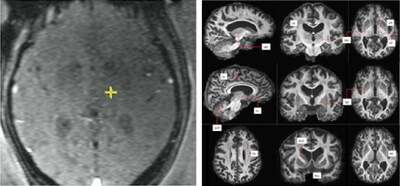

FAT1 Imaging Revolutionizes Essential Tremor Treatment

The study concerns a new imaging technique called FAT1, developed by consultant neurosurgeon Mr. Harith Akram, which is designed to improve the accuracy and outcomes of MR-guided focused ultrasound (MRgFUS) treatment for patients suffering from essential tremor. This technique, which fuses multiple MRI scan types, aims to overcome the difficulty of visualising the small target area in the brain (the Vim nucleus) during the non-invasive procedure. Continue reading